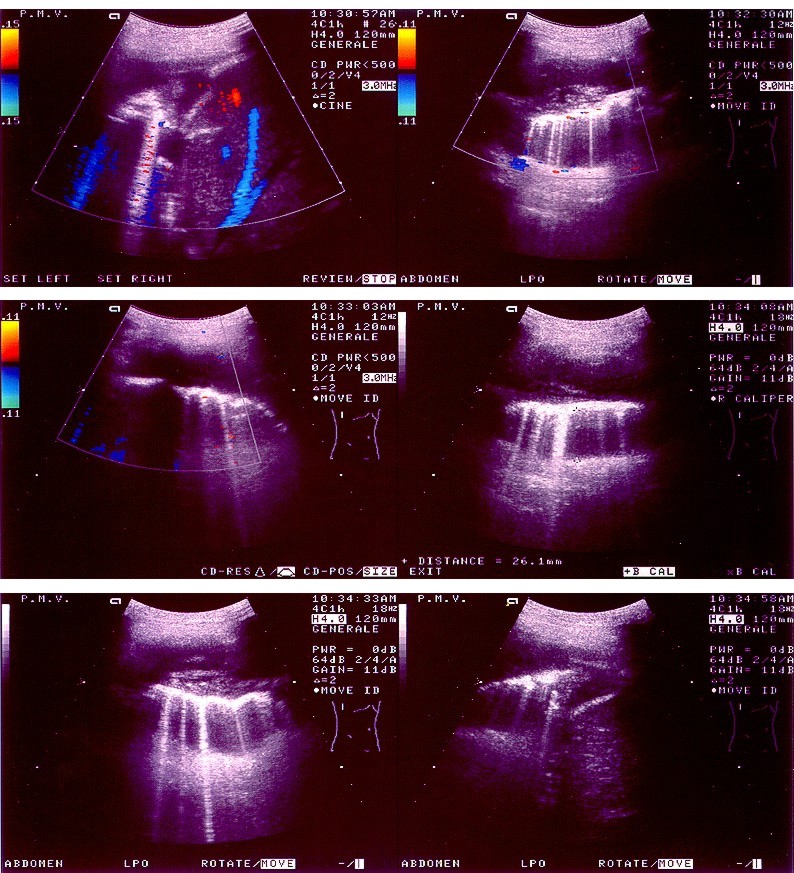

Il mesotelioma pleurico è un tumore associato alla pleura, la membrana che avvolge i polmoni. È spesso causato dall’esposizione alle fibre di amianto, che in passato era contenuto in alte concentrazioni in prodotti come materiali per l’edilizia e spray antincendio. Questa forma di cancro può non manifestarsi anche per cinquant’anni; per questo motivo, sebbene i materiali che lo contengono siano stati messi al bando da tempo, ogni anno in Italia oltre mille persone scoprono di soffrirne. I sintomi – fiato corto, dolore al petto e tosse persistente – caratterizzano anche altre patologie. Attualmente la diagnosi si basa sull’analisi delle effusioni, ovvero dei liquidi che si accumulano tra le pleure, ma nell’85 per cento dei casi i risultati sono poco accurati e non decisivi.